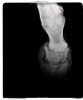

Перелом путовой кости (fractura articulationis phalangis primae) y лошадей может быть косым, продольным, поперечным, многооскольчатым.

Этиология. Направление щели перелома зависит от механизма действующей силы; при крутом повороте на опирающейся конечности чаще возникает косой (сегментальный) или продольный (от проксимальной до дистальной суставных поверхностей) перелом. В этом случае валик суставной поверхности пястной (плюсневой) кости при повороте расщепляет путовую кость на две части. Прыжок с упором на выведенную вперед конечность сопровождается поперечным переломом, обычно в нижней трети кости, редко многооскольчатым, иногда вколоченным переломом, отломом бугров. Относительно часто встречаются продольные трещины путовой кости.

Клинические признаки. В случае полного перелома они хорошо выражены. На поднятой конечности часто удается определить взаимоположение отломков. Труднее диагностировать трещину.

При этом обращают внимание на болезненность при надавливании на дорсальную поверхность кости, но и этот симптом недостоверен, так как болезненность в тех же участках пута возникает в связи с воспалением надкостницы дорсальной поверхности путовой кости, развивающемся при растяжении прикрепляющихся пучков сухожилий. В хронической стадии периостита формируются экзостозы передней поверхности путовой кости.

Прогноз благоприятный, за исключением случаев многооскольчатого перелома (возможно развитие деформирующего артрита, разрастание гипертрофической мозоли, анкилоз), а также случаев, когда не удается предотвратить развитие гнойной инфекции. Условия успешной консолидации кости при этом включают ограниченное смещение отломков, фиксированных один относительно другого связками и сухожилиями, прикрепляющимися к путовой кости, а также возможностью иммобилизации суставов пальца.

Диагностика. Диагноз ставят по клиническим признакам и уточняют при помощи рентгенографии.